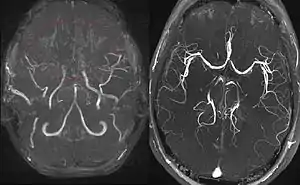

Right: healthy patient, for comparison.

Magnetic resonance angiography (MRA) is also useful in diagnosing the disease with good correlation with Suzuki's grading system.[15]